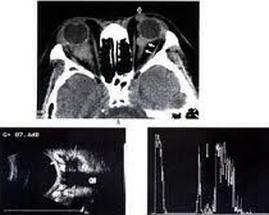

1.超声探查 由于淋巴瘤是由大量淋巴细胞组成,纤维组织间隔很少,A超显示病变内呈低反射,声衰减不明显,边界清楚,B超显示病变呈不规则形,扁平形或椭圆形,边界清楚,内回声少,声衰减轻,一般CDI常发现病变内有较丰富的血流。

2.CT扫描 多数肿瘤位于眼眶前部并累及包绕眼球,眼外肌或视神经,边界不清楚,形状不规则,增强明显,很少出现骨破坏,但可充满眼眶。

3.MRI 淋巴瘤多位于泪腺,眼睑,也可弥漫侵及眶内软组织,在MRI上TlWI多为中信号,T2WI为高信号,或中高异质信号,增强明显,由于病变呈浸润性增生,可显示包绕眼眶正常结构,甚至充满眼眶。